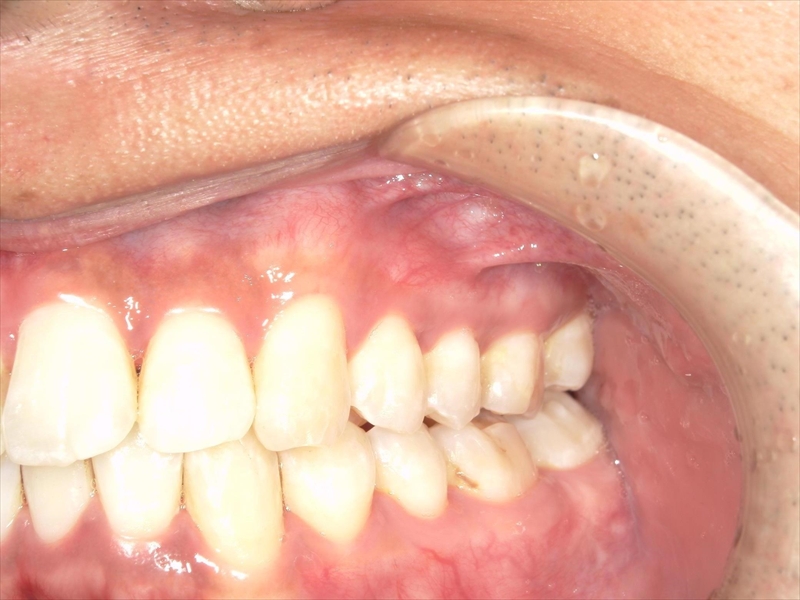

- 上あごの前歯がV字状の出っ歯

- 下あごの前歯もがたついている(叢生)

- 上あごに対して下あごがかなり小さい(過蓋咬合)

前歯のねじれ(V字)と出っ歯を下げるスペースを確保のため、両側1~5番目を0.2~0.5ミリ(計4ミリ)削ることと、奥歯から順に奥へ下げながら外側へ広げる計画を立案しました。

上あご同様、スペース確保のため、両側1~5番目までを各0.5ミリ(計5.5ミリ)削ることと、奥歯から順に奥へ下げながら外側へ広げる計画を立案しました。